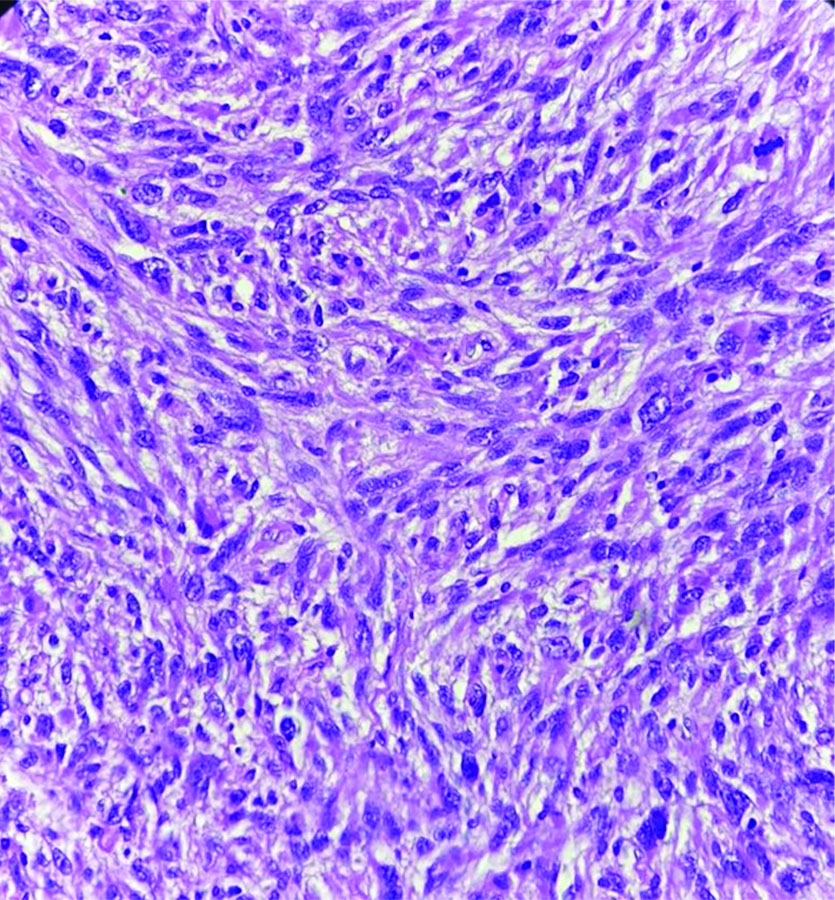

Following the cytodiagnosis, the patient underwent surgical resection of the tumour [Table/Fig-6]. The histopathology revealed pleomorphic spindle cells arranged in a fascicular arrangement. These cells exhibited scant wavy cytoplasm with marked anisonucleosis and a high N/C ratio. The hyperchromatic nuclei contained loose open chromatin, with nucleoli present in some. Mitotic figures were also observed. The histopathological features were suggestive of a malignant mesenchymal tumour [Table/Fig-7]. Immunohistochemical analysis confirmed the diagnosis of MPNST, showing diffuse positive immunoexpression for S-100 [Table/Fig-8] and SOX-10. The patient was followed-up by the Institute’s tumour board committee and was initiated on postoperative radiotherapy and chemotherapeutic drugs such as doxorubicin and ifosfamide as part of the adjunctive treatment plan.

Section shows hypercellular neoplasm composed of pleomorphic spindle cells with a high N:C ratio. Occasional mitotic figures are seen (H&E, 40x).